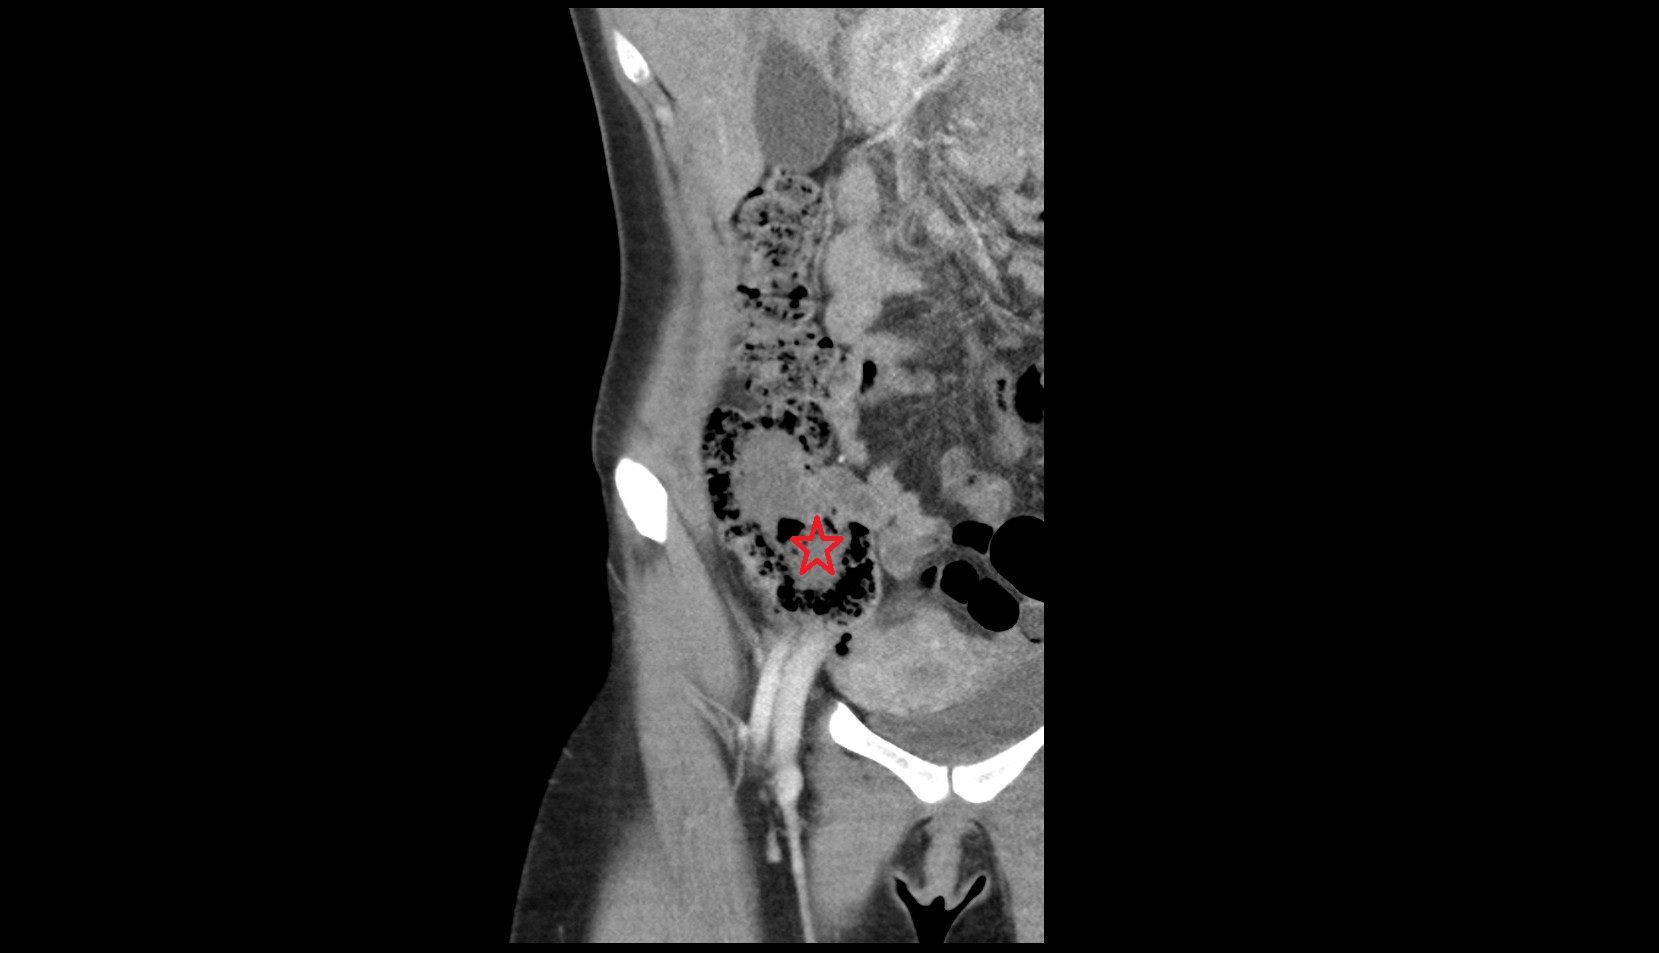

- Rectum

- Mesorectal fascia

- Mesorectum

- Mesorectal free fluid